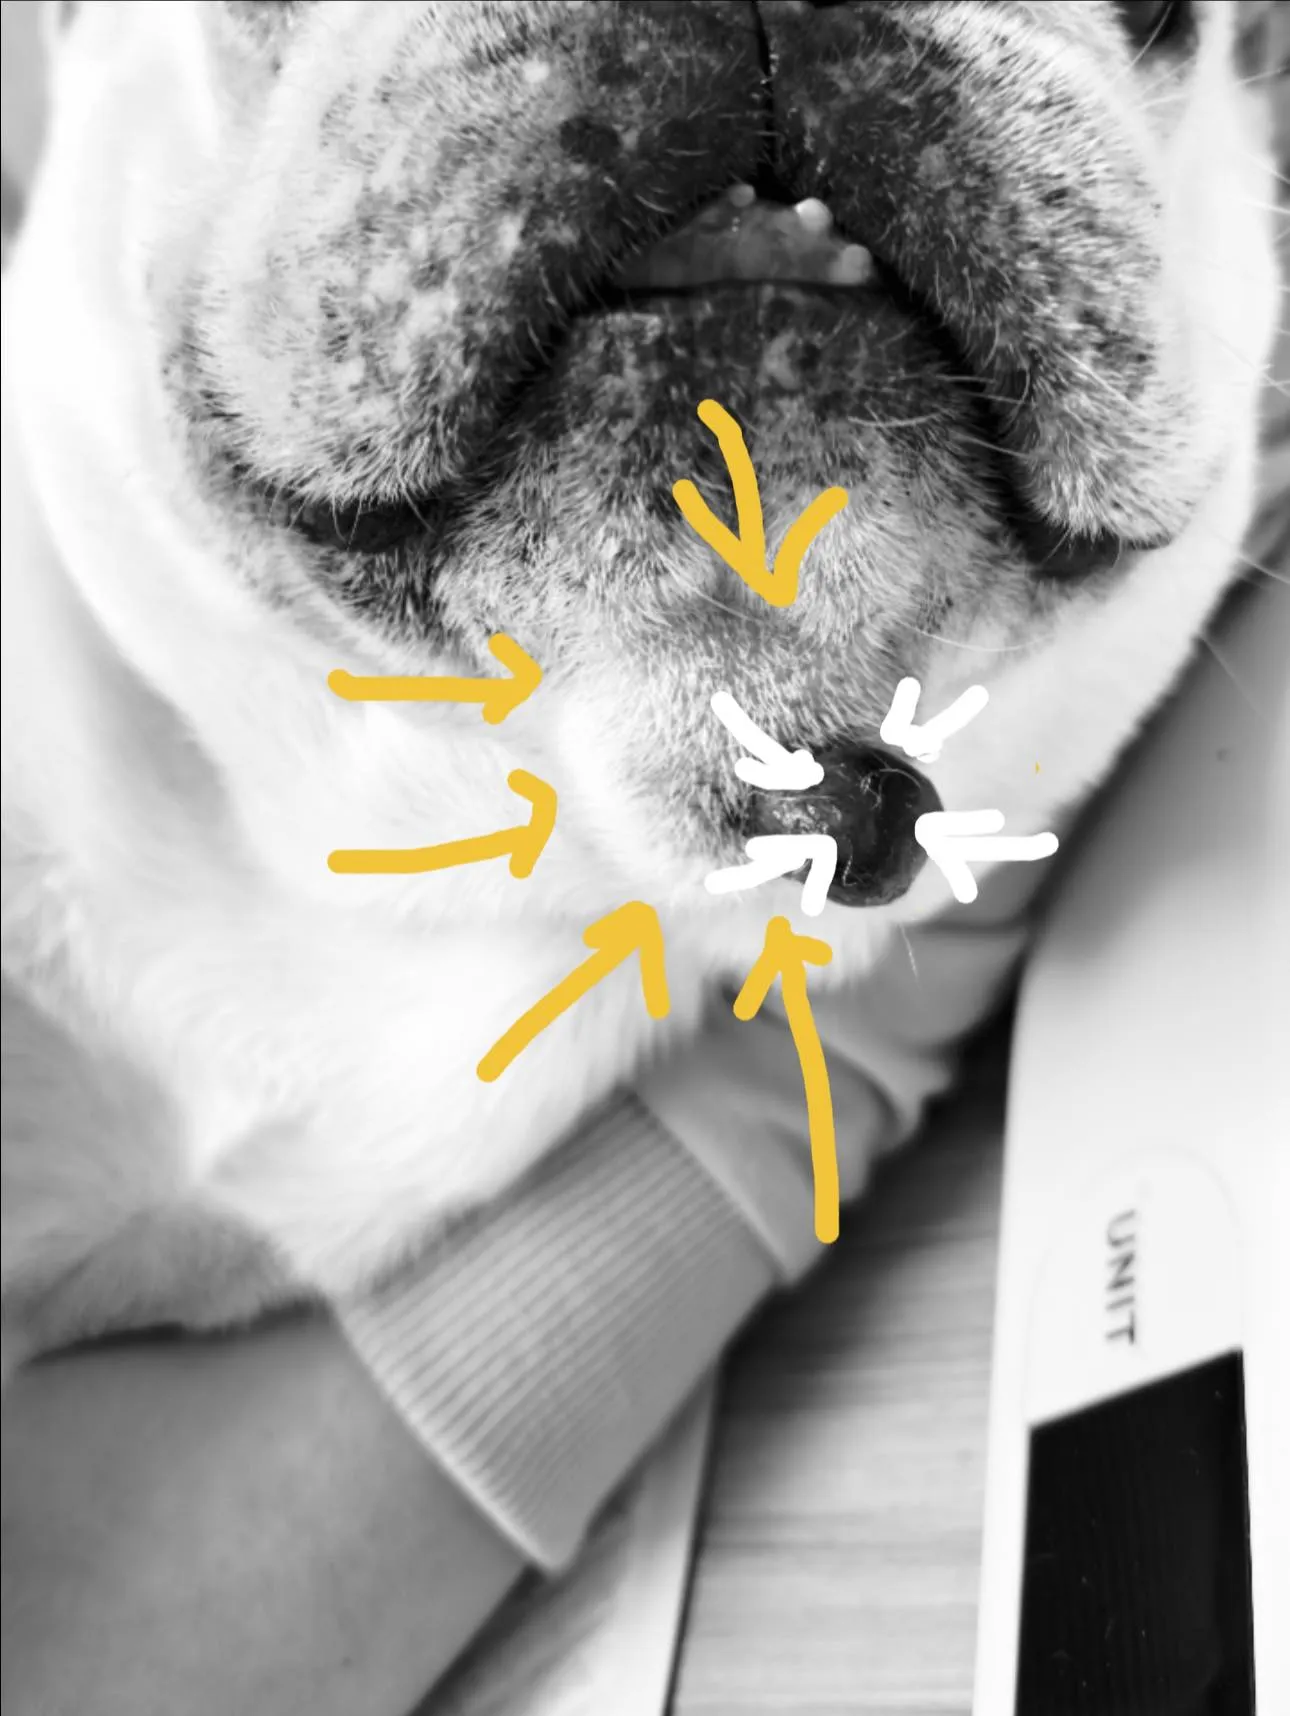

橘白小貓小虎突然肚子鼓鼓的,飼主以為是變胖,結果發現牠精神差、食慾不好,到院後一照超音波,腹腔裡滿滿的腹水!

抽出的腹水呈黃色黏稠,血檢球蛋白很高——高度懷疑是傳染性腹膜炎(FIP)。

橘白小貓小虎突然肚子鼓鼓的,飼主以為是變胖,結果發現牠精神差、食慾不好,到院後一照超音波,腹腔裡滿滿的腹水!

抽出的腹水呈黃色黏稠,血檢球蛋白很高——高度懷疑是傳染性腹膜炎(FIP)。